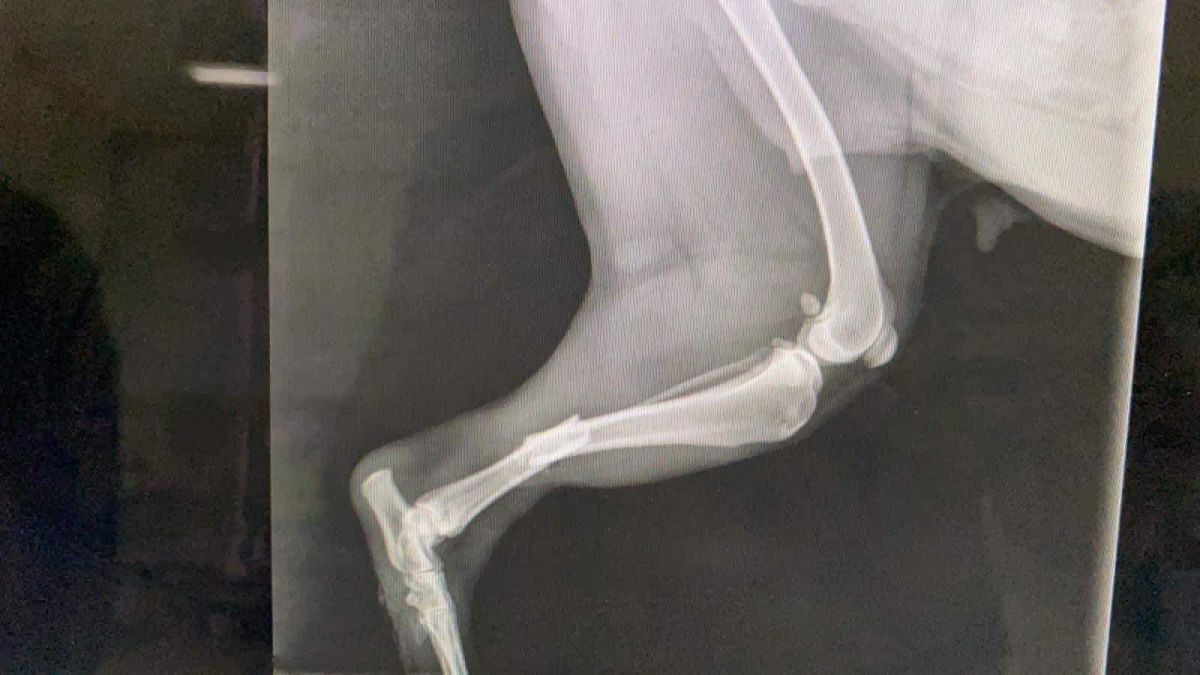

Prinsă în laț și bătută cu atâta cruzime încât i-au rupt picioarele, cățelușa a fost adusă de niște oameni miloși în cabinetul medicilor veterinari.

În urma investigațiilor și radiografiilor s-a confirmat că ambele membre posterioare prezentau fracturi duble, unul din membre cu fractura semideschisă, însă încă prezentau sensibilitate”,

Operația s-a realizat de urgență, totul a decurs bine, dar există în continuare risc de infecție, astfel că va mai rămâne internată câteva zile în clinică, recuperarea fiind una de durata.